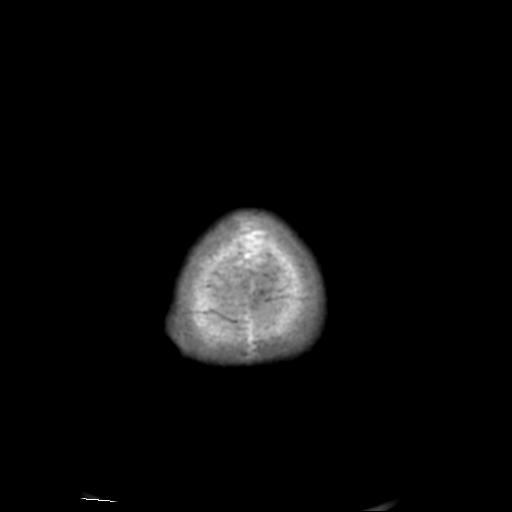

CT50972:颅骨病变,请会诊27751

患者:女,75Y,不省人事半小时入院。

骨化性纤维瘤可能。

考虑血管瘤可能,骨纤待排

考虑血管瘤可能,骨纤待鉴别

骨化纤维瘤

嗜酸性肉芽肿?

血管瘤可能性大。

血管瘤可能。